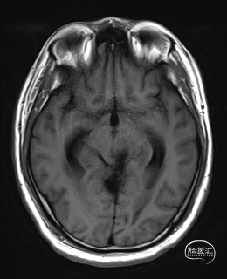

术前MRI检查

术前MRI检查提示左侧丘脑中脑海绵状血管瘤并卒中,梗阻性脑积水;

根据MRI及DTI显示,只有在丘脑与上丘之间的点(dot)进入病变才可能在切除病变时最大程度保护神经功能,由于上述原因,该“点”在术中显露极其困难,虽有导航指引,电生理监测的条件下,对术者的耐心、技术、经验及体能依然是极大的挑战;

本例患者磁共振检查清晰显示病变位于左侧丘脑中脑区域,且位于丘脑内下方向中脑顶盖延续,病变的上部、前部、外侧部都有重要的神经组织,因此,手术从上方、前方、外侧方向切除病变均难以实施;

术前详细的磁共振检查,包括平扫增强,SWI及DTI,可以规划出手术最适宜的路径及切入点;